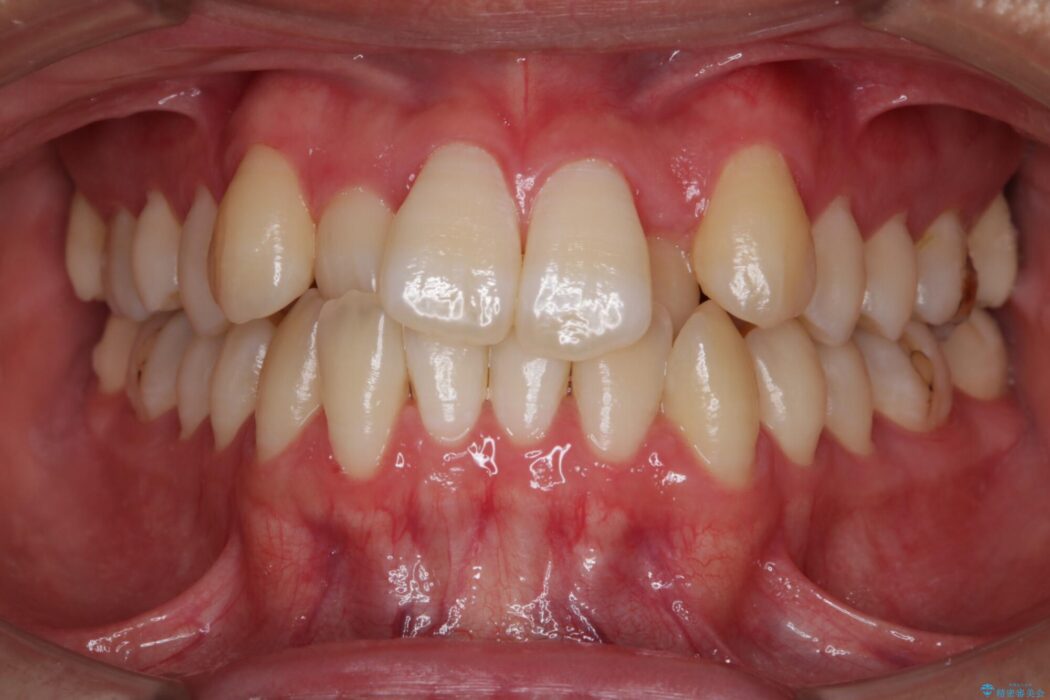

治療動機

上顎歯列弓のガタガタを治療したいとのことで来院されました。

目立たない矯正装置をご希望されていたため、インビザラインでの治療をご提案しました。